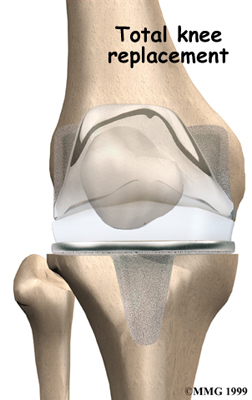

Artificial Knee Replacement

An artificial knee replacement is the ultimate solution for advanced knee OA.

Surgeons prefer not to put a new knee joint in patients younger than 60. This is because younger patients are generally more active and might put too much stress on the joint, causing it to loosen or even crack. A revision surgery to replace a damaged prosthesis is harder to do, has more possible complications, and is usually less successful than a first-time joint replacement surgery.

Related Document: FYZICAL Central Orlando's Guide to Artificial Joint Replacement of the Knee